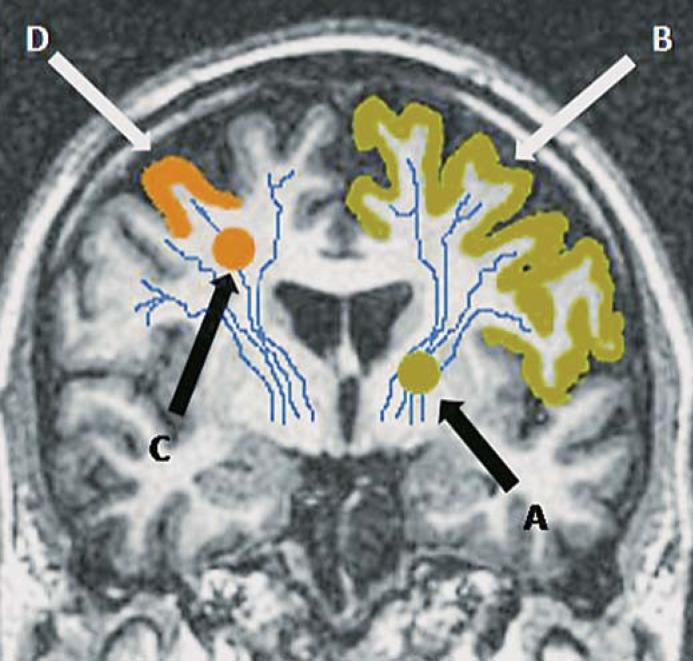

Up to 20% of lacunar infarcts are clinically misdiagnosed as cortical infarcts and vice versa. The reasons for this discrepancy are unclear. We assessed clinical and imaging features which might explain this 'clinical-imaging dissociation' (C-ID).

Patients with an acute stroke syndrome (cortical or lacunar) underwent magnetic resonance imaging including diffusion-weighted imaging (DWI). We recorded DWI-positive infarcts and proximity to cortex for small subcortical infarcts. We examined factors associated with C-ID.

137 patients with a mild cortical or lacunar syndrome had an acute ischemic lesion on DWI. Of these, 21/93 (23%) with a cortical syndrome had an acute lacunar infarct and 7/44 (16%) with a lacunar syndrome had an acute cortical infarct. From 72 patients with an acute lacunar infarct on DWI, lesion proximity to cortex (odds ratio (OR) 14.5, 95% confidence interval (CI) 1.61-130.1), left hemisphere location (OR 8.95, 95% CI 1.23-64.99) and diabetes (OR 17.1, 95% CI 1.49-196.16) predicted C-ID. On multivariate analysis of all 137 patients, C-ID was associated with diabetes (OR 7.12, 95% CI 1.86-27.2).

C-ID occurs in a fifth of patients with mild stroke. Lacunar infarcts lying close to cortex are more likely to cause cortical symptoms. Diabetes is associated with any clinical-imaging mismatch. Stroke misclassification which can arise with clinical classification alone should be minimized in research by verification with high-sensitivity imaging.